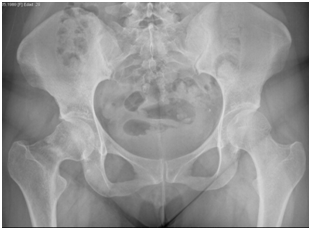

Female patient of 25years-old, active military, size 165cm, weight 52kg, BMI 19.1, with antecedent of military training for about 5 to 6hours a day, 6days a week, for 2months prior to the onset of symptomatology. She refers with discrete right inguinal pain, which increased with physical effort, radiating towards the proximal third of the thigh and right buttock. It is evaluated by a general physician and diagnosed as a muscle contraction, without abnormalities in the x-ray exam (Figure 1) indicating treatment with analgesics and non-steroidal anti-inflammatory drugs, without suspension of physical activities. She comes back to the emergency department of the Naval General Hospital of High Specialty one week later, referring an acute increase in the symptoms and limitation of movement due to pain, an antero posterior pelvic radiograph is performed, without data of apparent bone lesion (Figure 2).

Figure 2 01/09/2015 anteroposterior pelvic radiograph, taking in the follow up, without no data of apparent bone lesion.